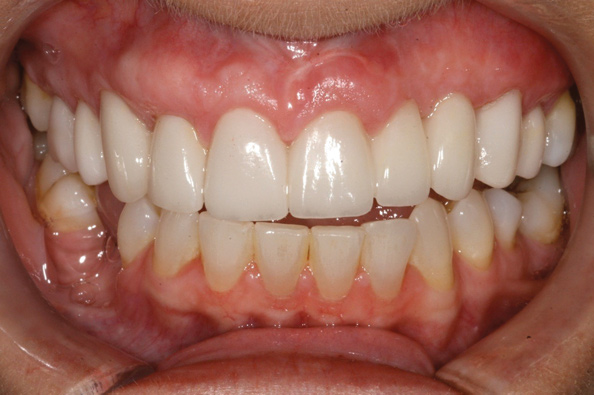

Fig 2. Miller Class I recession on tooth No. 11 (Fig 1) treated with tuberosity CTG (Fig 2). Note this CTG (which is the tuberosity CTG from Fig 5) was placed before the practitioner developed thinning techniques, so a keloid-like appearance was observed even 1 year after grafting.

Figure 2

Fig 3. Tooth No. 28 had a Class V filling that failed with recurrent decay (Fig 3). A tuberosity CTG with a 1.5 mm thickness was placed, and after 1 year there was no keloid-like appearance (Fig 4).

Figure 3

Fig 4. Tooth No. 28 had a Class V filling that failed with recurrent decay (Fig 3). A tuberosity CTG with a 1.5 mm thickness was placed, and after 1 year there was no keloid-like appearance (Fig 4).

Figure 4

A complication in using CT from the tuberosity reported in the literature is a tendency for clinicians to harvest tissue that is too thick.12 This can result in a keloid-like appearance similar to what may occur with an EPG. This excess thickness can be unesthetic (Figure 1 and Figure 2) and subsequently require a gingivoplasty to remove the superfluous tissue.12 This problem may perhaps be alleviated with proper thinning of the graft prior to insertion into the recipient area.

Regarding the avoidance of a gingivoplasty procedure later, there appears to be nothing in the literature describing the ideal thickness of a tuberosity CTG. From palatal and allograft thickness recommendations, one could hypothesize that the thickness be between 0.75 mm and 2 mm. This article will propose a graft thickness between 1 mm to 1.5 mm (Figure 3 and Figure 4) for the optimal functional and esthetic outcome and will discuss various procurement and fileting techniques.

Class V fillings are artificial materials that tend to fail at the apical extent and have poor long-term success (Figure 3).1 Conversely, CTGs are natural and attach to the root surface and have high long-term success (Figure 4).1

Dense CT presumably is less susceptible to shrinkage than less-dense CT. One problem with denser CT may be the need for a longer amount of time to blend in with adjacent non-grafted areas. Due to density, a CT graft might never completely blend in and always demonstrate an unesthetic keloid-like appearance. Therefore, with tuberosity tissue, adjusting the tissue thickness prior to placement of the graft is highly clinically relevant. This may be why periodontists have been reluctant to use tuberosity tissue as CT. Palatal tissue has less-dense CT than tuberosity tissue and, therefore, the authors hypothesize and have observed, shrinks more. Because palatal tissue has been the predominant tissue used in CTG, clinicians have become used to the shrinkage associated with the palatal CT and may not realize the need to thin a dense CTG to prevent a keloid-like appearance. Thus, in the past when a tuberosity was used for this purpose, if it was not properly trimmed it would have frequently resulted in an unesthetic keloid-like appearance. The tuberosity CTG should be trimmed to 1 mm to 1.5 mm thick to avoid the need for a future procedure to adjust tissue thickness for esthetics (Figure 3 and Figure 4, Figure 16 and Figure 17).